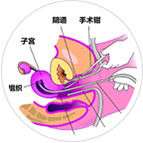

LEEP刀 宫腔镜

设备是一切技术的基础,是诊断疾病的基石。广州花都时代妇产医院整合妇科医疗资源,积极学习新的诊疗技术、理念和方法。先后购入腹腔镜、宫腔镜,彩色多普勒超声诊断仪,无痛保宫人流系统、Drager麻醉机、盆底康复治疗仪(子宫修复)等新诊疗设备,为疾病诊断提供科学依据。